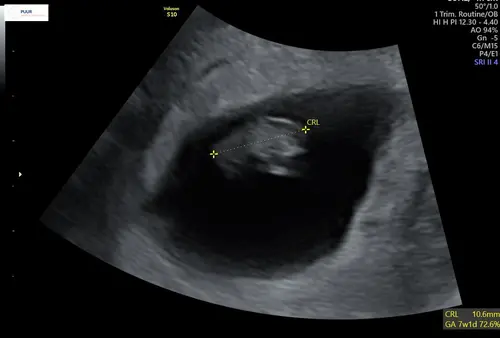

Uitwendig! Sorry vergeten te benoemen

ik denk meisje馃┓

CHATGPT zegt met deze uitwendige echo een meisje, wat denken jullie? Ik heb ...

Ja heel lastig lijkt het maar je moet eigenlijk naar de ligging / locatie van je placenta kijken. Ik denk ook een meisje馃┓